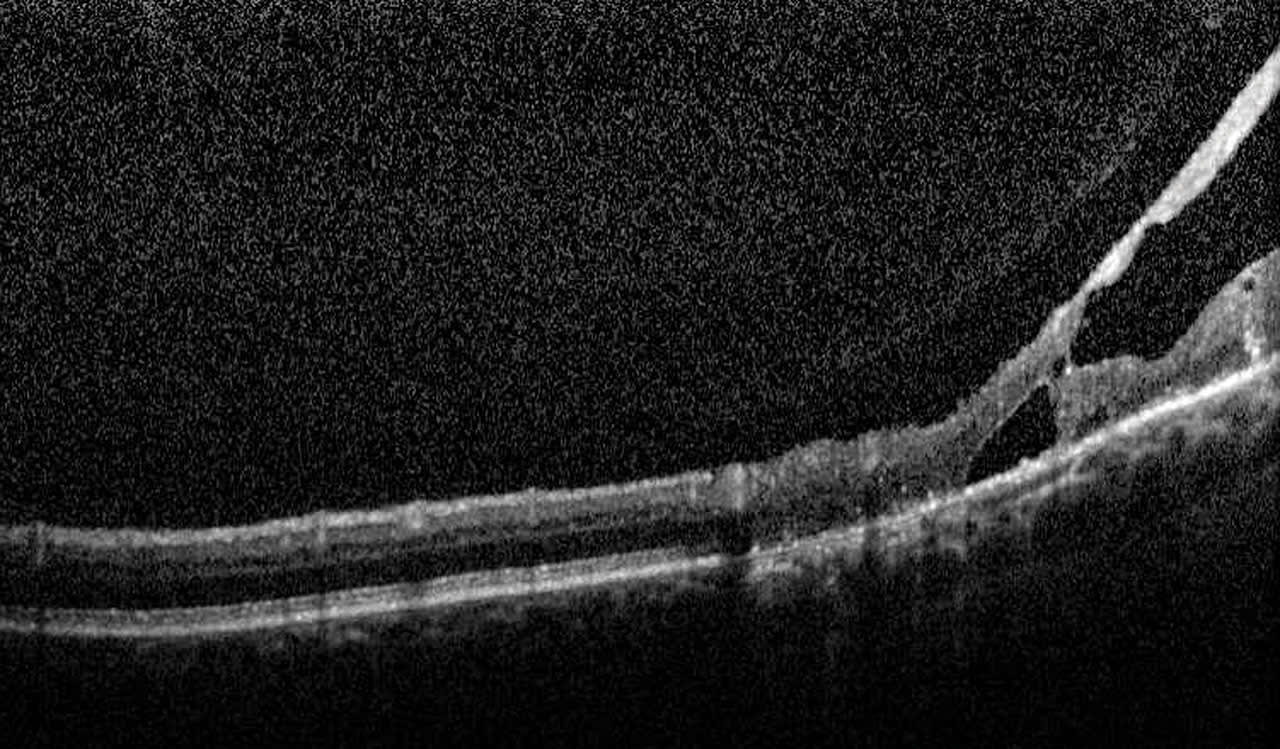

Outer retinal tubulation (ORT) is another instance where OCT provides prognostic value. ORT are tubular structures typically found in the outer nuclear layer in advanced AMD4 and are the scrolling of the external limiting membrane and photoreceptor inner segments, the result of restructuring of degenerative photoreceptor cells. They are easily identified by the hyperreflective band and hypo-reflective cavity (Figure 10). In the presence of ORT, the prognosis for recoverable vision is very unlikely.5